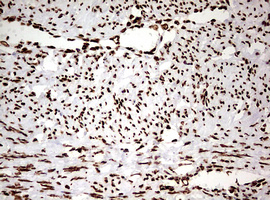

Immunohistochemical staining of paraffin-embedded Carcinoma of Human liver tissue using anti-HNRNPM mouse monoclonal antibody. (Heat-induced epitope retrieval by 10mM citric buffer, pH6.0, 120°C for 3min, M06017-2)